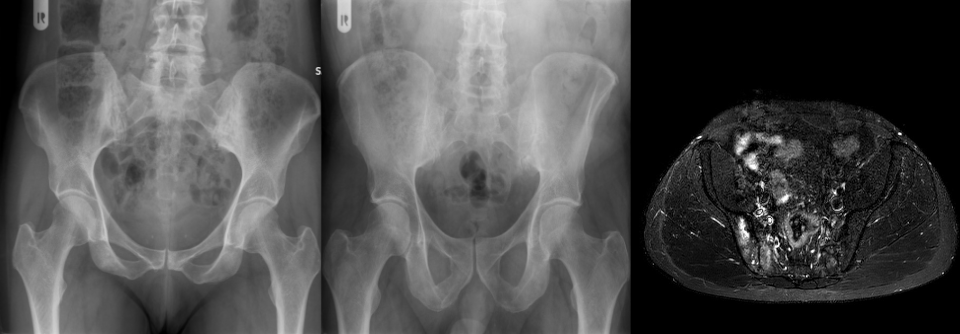

Schlussendlich ist in vielen Fällen das traditionelle Röntgenbild ein guter Berater. Polyarthrose, rheumatoide Arthritis und Chondrokalzinose lassen sich durch Lokalisation und Art des Befalls meist gut identifizieren.